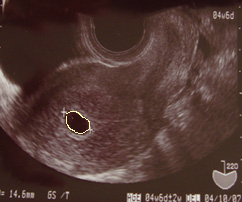

8W

←心音がはじめて確認されたときのエコー。

下の丸が赤ちゃん。真ん中あたりがトクトク動いてて、見たとき”生きてるんだなぁ”っと感動。

ちなみに、赤ちゃんの大きさはピーナッツくらい

上の丸が卵黄嚢【らんおうのう】っといって赤ちゃんの栄養になっているらしい。

心音が確認されてから、赤ちゃんの様子を家の人も見れるようにと、毎回エコーをビデオにとってくれます。

この頃ずっとお腹が痛くて、生理痛のような痛みがあって、流産してしまうんじゃないかと毎日毎日心配でした。

結局その痛みは、子宮をつくっているための痛み+血行の悪さwwからということで大事にはいたらなかったのですが、未だにこのとき処方された漢方薬を飲んでいます

まだ小さすぎて胎動を感じない上、たいしたつわりもないので、赤ちゃんを感じるには、産婦人科で見てもらうしかなかったので、医者に行きたくて行きたくてしかったなかった時期でした。次の診察日が待ち遠しくて1日がほんとに長かった。